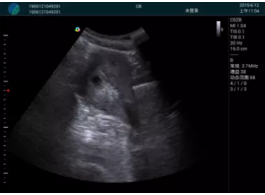

清晰顯示孕囊,通過軟件包計算孕齡7w+6d

M20實(shí)時引導(dǎo),術(shù)中清晰顯示孕囊被破壞和抽吸針的過程,清晰顯示吸引針

抽吸結(jié)束后縱切子宮,孕囊已被完全抽吸,未見明顯殘留